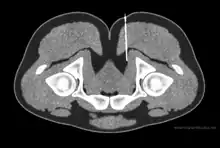

Diagnostic nerve blocks are very effective for identifying sensory entrapment points. Their strength is that they can directly measure whether a given nerve is contributing pain, or not. They are precise and reproducible.[36] As successful blocks require accurate targeting of the nerve, this is done under image guidance such as fluoroscopy, ultrasound,[37] CT,[37] or MRI.[38] Ultrasound is popular choice because of its soft-tissue contrast, portability, lack of radiation, and low cost, but is not good at depicting deeper structures like the deep pelvic nerves. For deeper structures, CT and MRI are more appropriate, although the equipment is more expensive.[39][40][41][37][38]